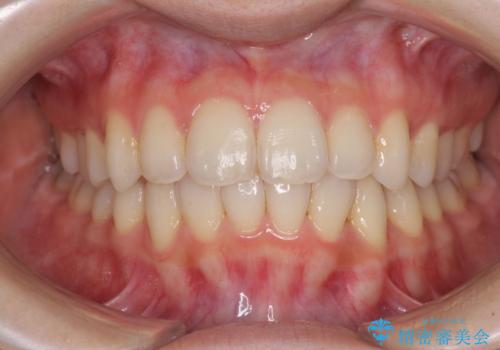

- 前歯のデコボコを気にして来院された患者様です。

叢生と捻転が随所に認められるものの、マウスピースで十分対応可能であったため、インビザラインにて矯正治療を行うこととしました。

マウスピース矯正は毎日しっかりと装着することがとても大切です。

こちらの方はしっかりと指示を守って装着してくださったため、予定通り治療を終えることができました。